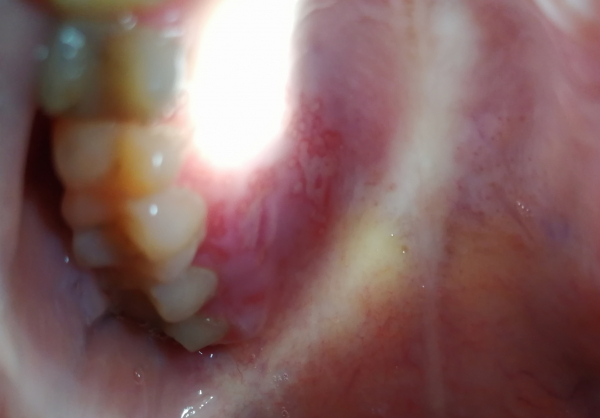

Неделю назад я обожгла нёбо, в нескольких местах. Пузырь почти сразу сорвался. Меня смущает, что нёбо долго заживает и болит, и странные точки вокруг одного из обожженных мест. Так же странные точки с другой стороны. Второй день полощу содой и мажу Солкосерилом. Боль немного уменьшилась.

Возможно из-за курения? Стоит ли бить тревогу или заживет со временем?

К сожалению, по фото, нельзя выявить причину ваших жалоб. Необходима очная консультация, осмотр и подробный сбор анамнеза. Обратитесь на прием к стоматологу-терапевту.